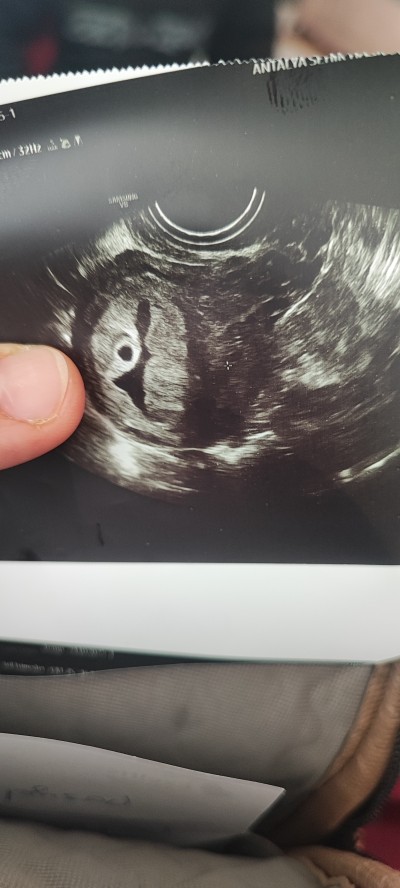

Anladım canım ben foto eklicem bak üzüm salkımı gibi durmuyormu

Ya hafif bı benzerlik var ama emin ol belki beta degerin yüksek olmasa onu bile anlamicaklardi yine de emin olmadan işlem yaptırma hayırlısı neyse o olsun

Bu resim sağda üzüm salkımı gi o duruyor